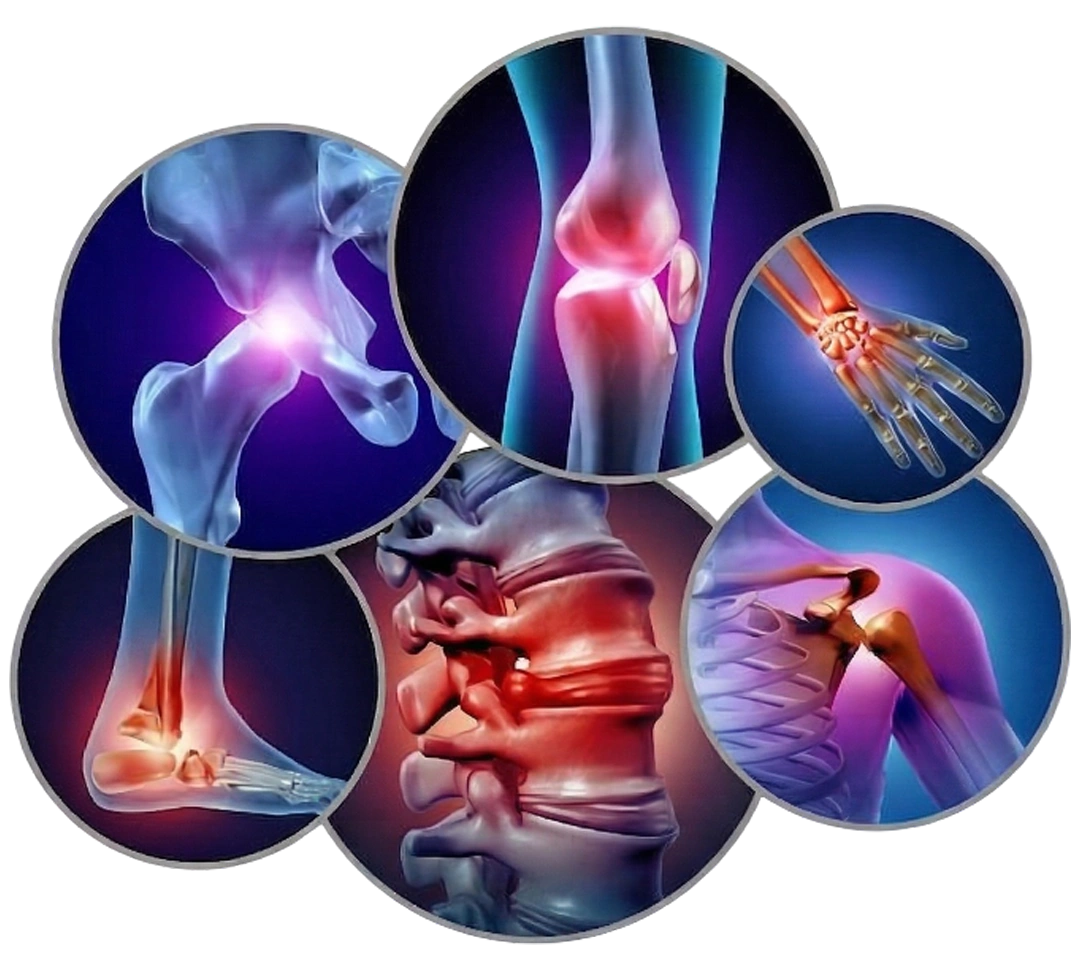

OrthoPro Clinic And Trauma Centre is a dedicated orthopaedic facility located inside Oscar Superspeciality Hospital, Goregaon West, Mumbai. We provide comprehensive bone, joint, and spine care using the latest minimally invasive techniques.

From emergency trauma management to elective procedures like knee replacement, arthroscopy, and spine surgery - our goal is to restore your mobility and improve your quality of life.